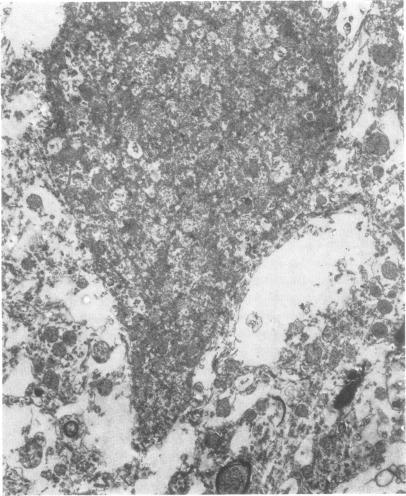

The morphological characteristics of brain death were examined in baboons and cats after artificial cerebral ischaemia. All animals showed autolytic changes in the brain, ischaemic neuronal changes, midbrain haemorrhages, focal necrosis of the brain-stem, demarcation at C 1/C 2 cord segment, and displacement of cerebellar tissue. Ultrastructural examination revealed extreme brain oedema, autolytic changes, and complete obstruction of capillaries by astrocytic and endothelial swelling and intravascular blebs. These data indicate that brain death develops in several stages. If the process starts in the supratentorial space it first leads to a breakdown of the cerebral circulation and to transtentorial herniation. As a result, midbrain haemorrhages develop and the infratentorial pressure begins to rise. The second stage is terminated by demarcation of the brain. The circulatory arrest is initially caused by venous compression but becomes irreversible when vascular obstruction develops.

在狒狒和猫身上进行人工脑缺血后,对脑死亡的形态学特征进行了检查。所有动物均表现出脑自溶变化、缺血性神经元变化、中脑出血、脑干局灶性坏死、C1/C2脊髓节段分界以及小脑组织移位。超微结构检查显示极度脑水肿、自溶变化,以及星形细胞和内皮细胞肿胀及血管内气泡导致毛细血管完全阻塞。这些数据表明脑死亡分几个阶段发展。如果该过程始于幕上空间,首先会导致脑循环中断和经天幕疝形成。结果,中脑出血发生,幕下压力开始升高。第二阶段以脑分界结束。循环停止最初是由静脉受压引起的,但当血管阻塞发生时就会变得不可逆转。